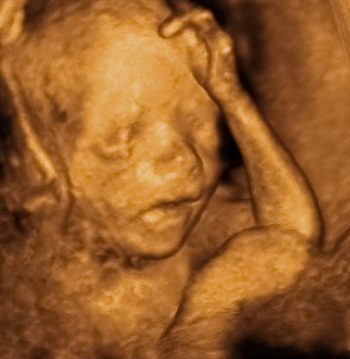

Panka 22 hét 4 naposan. 4D Genesisben készült.